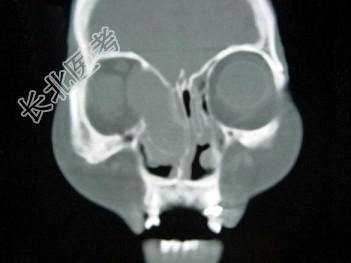

- 单项选择题女,40岁, 右眼反复溢泪伴眼球渐进性突出2年余,眼球运动受限, CT检查如图所示,最可能的诊断是 ( )